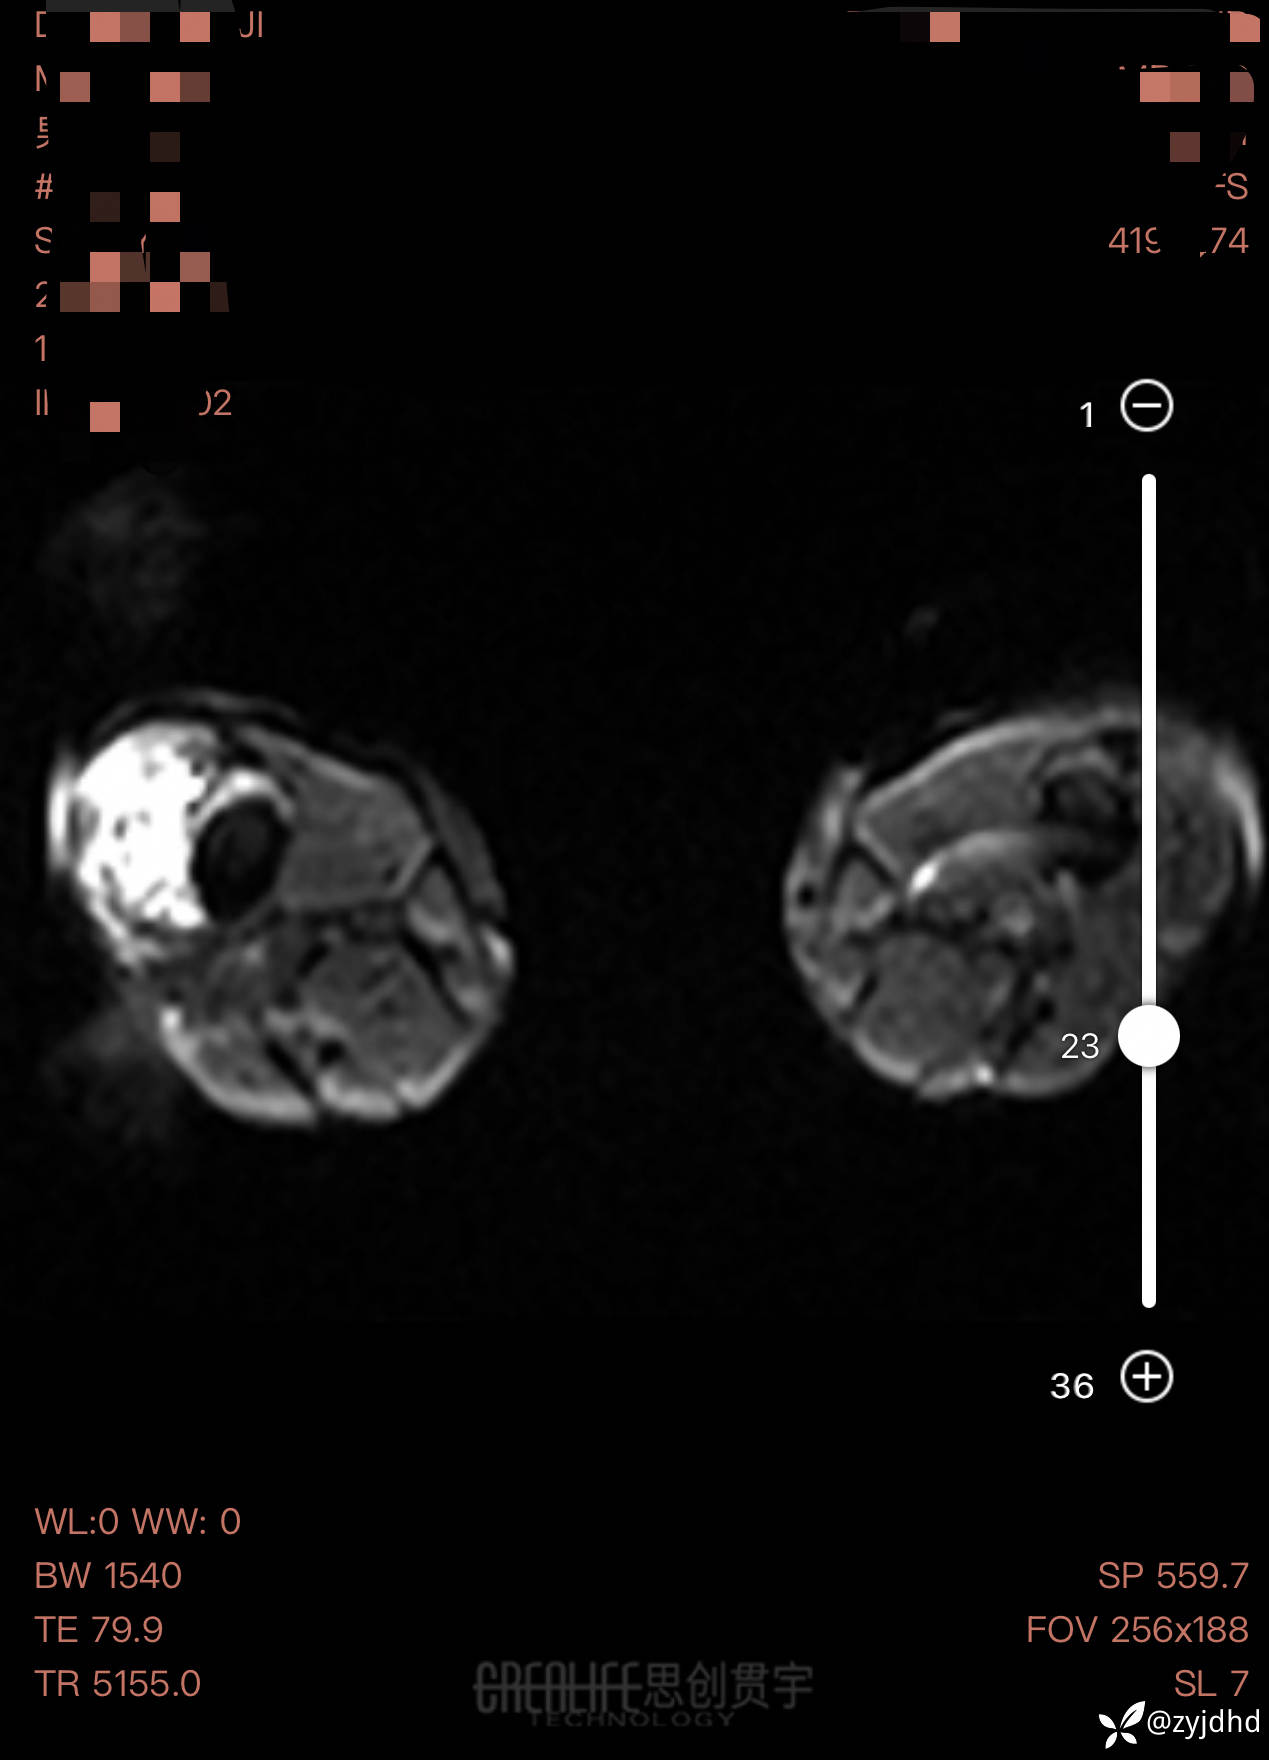

男性,发现右大腿肿物20年。

考虑什么诊断?治疗方案